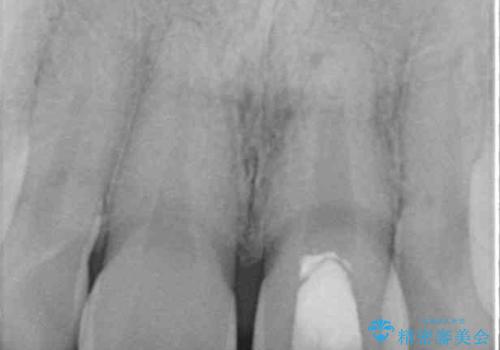

レントゲン写真より、歯の中の神経組織が失活していることが分かったため、根管治療、ファイバーコアによる土台築製を行い、オーダーメイドタイプのオールセラミッククラウンにて補綴することとしました。